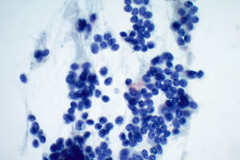

Cytology:

Aspirates of MTC are moderately cellular, showing a single cell pattern with occasional clustering and small aggregates. Cytologically, tumor cells can appear plasmacytoid, polygonal, or with spindle cells. Cells are uniform in size, but rare large pleomorphic cells may be present. The chromatin shows a coarse, granular, neuroendocrine pattern with inconspicuous nucleoli. Intranuclear inclusions may be seen, and nuclear grooves are rare. The cytoplasm is granular, and the amount is variable and rarely scant. Cytoplasmic dendritic processes may also be seen. Amyloid may be present in the background, although it can be identical to colloid in Papanicolaou-stained specimens. Variants of MTC include a follicular variant, papillary variant, small cell variant, giant cell variant, and a clear cell variant7. Cell blocks of MTC typically stain positive for calcitonin, CEA, TTF1, synaptophysin, and chromogranin, and are negative for thyroglobulin and PAX-88,9.

The tumor cells of this case presentation posed a diagnostic challenge due to their divergence from the typical cytological appearance of MTC. The majority of tumor cells had scant cytoplasm, including cells that resembled naked nuclei and cells with a plasmacytoid appearance. A diagnosis of MTC was rendered in conjunction with the patient’s elevated calcitonin level, history of MTC and MEN2, and comparison to the patient’s previous two MTC diagnoses.